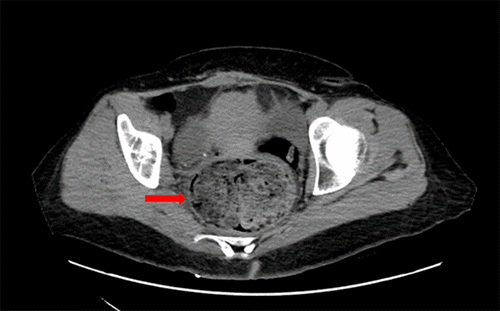

The patient was admitted to the medical ICU for hypertensive emergency and stabilized on nicardipine infusion, which was transitioned days later to a combination of oral nifedipine, doxazosin, and labetalol. An MRI scan of the abdomen and pelvis further defined the adrenal findings as bilateral lobulated, exophytic T2-intense lesions arising from the adrenal glands with cystic areas, consistent with hemorrhagic product (Figure 2).

Figure 2. Adrenal Gland Masses Demonstrated on MRI. Published with Permission

A) Axial and B) coronal MRI showing a 7.4 × 7.2 × 11.6 cm heterogeneous mildly T2 hyperintense lobulated lesion arising from the right adrenal gland (red arrows). A 9.9 × 9.1 × 8.3 cm heterogeneous lobulated exophytic lesion with an area of cystic/necrotic changes arising from the left adrenal gland (yellow arrows). These lesions likely contain hemorrhagic complement